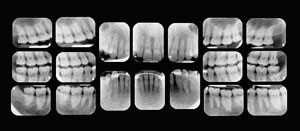

Your first visit to the doctor typically includes an x-ray that allows the doctor to view the structure of the jaw, the position of any teeth that have not yet erupted, malformed roots, and tooth decay.